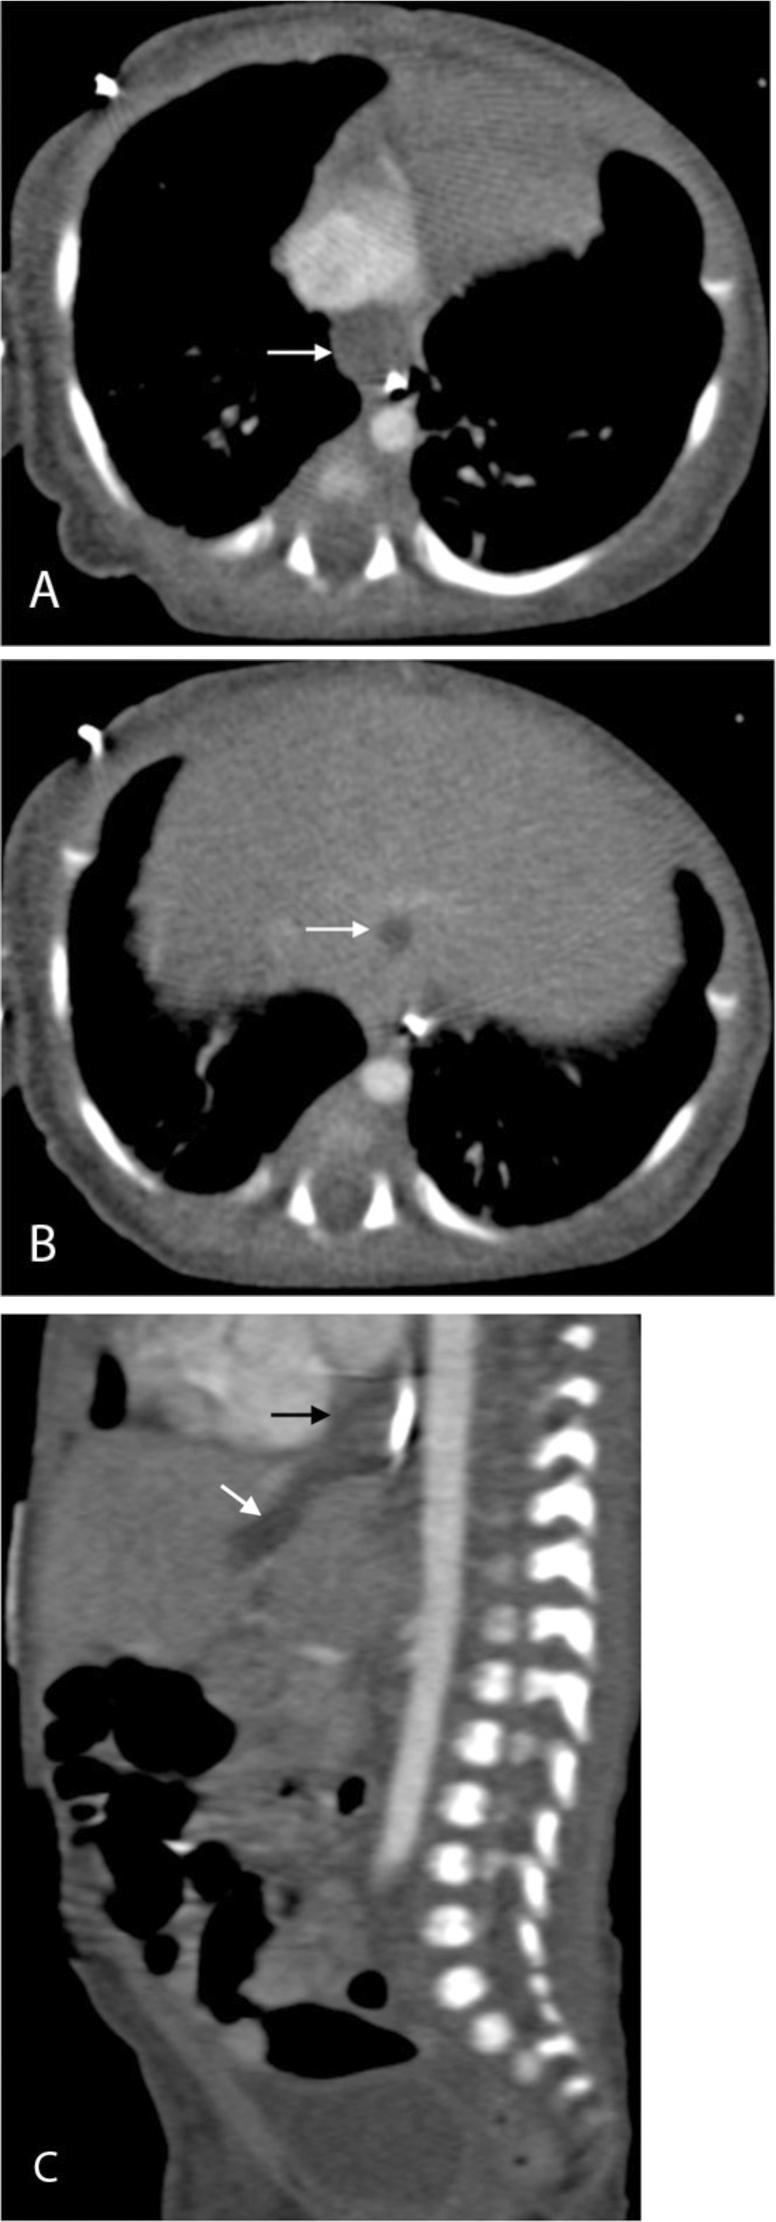

Congenital tracheobiliary or bronchobiliary fistula is a rare developmental anomaly with a persistent communication between the biliary system and the trachea or bronchus. We report a case of a congenital tracheobiliary fistula and hypoplastic common hepatic duct associated with hypoplastic left heart syndrome in a 5-day old boy presenting with bilious endotracheal-tube secretions. The tracheobiliary fistula was treated by surgical resection. Subsequent cholangiography demonstrated dilated intrahepatic bile ducts and a residual fistulous tract with cystic proximal stump that were successfully decompressed by transhepatic drainage catheters before corrective biliary surgery.

先天性气管胆管或支气管胆管瘘是一种罕见的发育异常,其特征为胆道系统与气管或支气管之间存在持续的连通。我们报告了一例5日龄男婴,患有先天性气管胆管瘘、肝总管发育不全并伴有左心发育不全综合征,该患儿出现胆汁性气管插管分泌物。通过手术切除治疗气管胆管瘘。随后的胆管造影显示肝内胆管扩张以及存在残余瘘管,其近端呈囊性残端,在进行矫正性胆道手术前,经肝引流导管成功对其进行了减压。